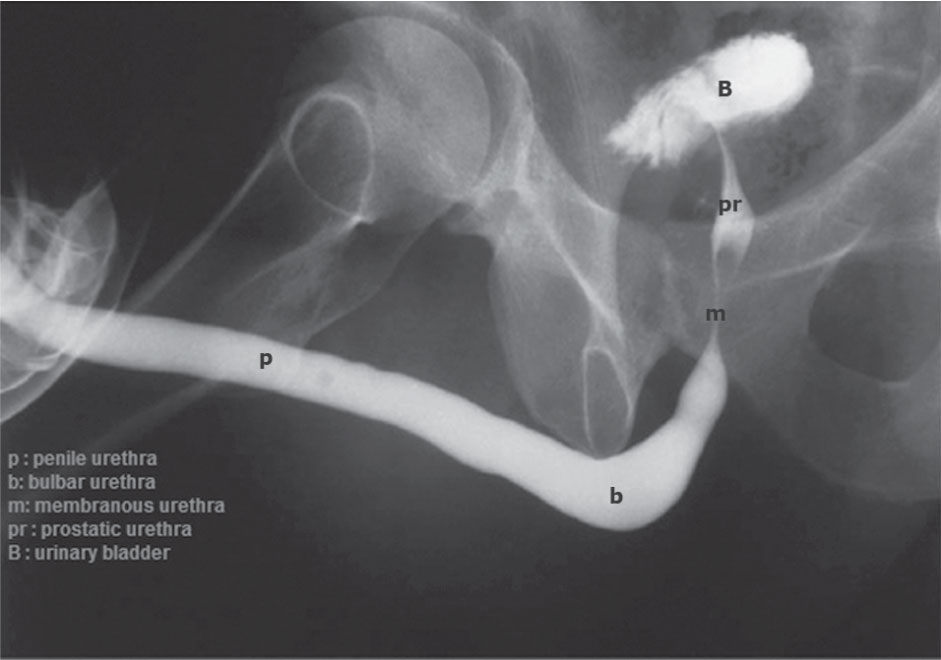

-7 تصوير الإحليل بالطريق الراجع :retrograde urethrography

يعد الفحص الأمثل لدراسة الإحليل عند الرجال.

الطريقة: تحقن مادة ظليلة في صماخ الإحليل وتحت التنظير الشعاعي مع أخذ صور للإحليل بأقسامه المختلفة (الشكل 6).

الاستطبابات: تفيد هذه الصورة في تقييم تضيقات الإحليل والنواسير والرتوج والبحث عن أورام أو حصيات في الإحليل. كما تستخدم هذه الصورة لتقييم رضوض الإحليل وتمزقاته. وتجدر الإشارة إلى أن هذه الصورة ليست مفيدة في تقييم دسام الإحليل الخلفي ودراسته عند الأطفال، ولا بد في هذه الحالة من دراسة الإحليل في أثناء التبويل كي يتم إظهار الدسام.

الشكل (6) صورة للإحليل بالطريق الراجع تظهر فيها أقسام الإحليل المختلفة الأمامي والغشائي والموثي.  |